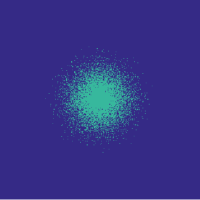

![]() |

Figure 6 (Left) illustrates that the learning-based approach outperforms the randomized variable-density approach. Note that here we use the function with , as introduced in Section II-D. We use Hadamard sampling, since it is easy to implement in digital hardware [28]. The density function of [3] is parametrized by the radius of fully sampled region, , and the polynomial degree, . We choose the parameters’ values that yield the lowest reconstruction error on the training set for each compression rate in the ranges and , taking the best realization over 20 random draws in each case.

Figure 6 (Left) shows example reconstructions at and compressions. A likely reason for the reduced error due to our approach is that we do not assume any shape for the distribution of the indices.